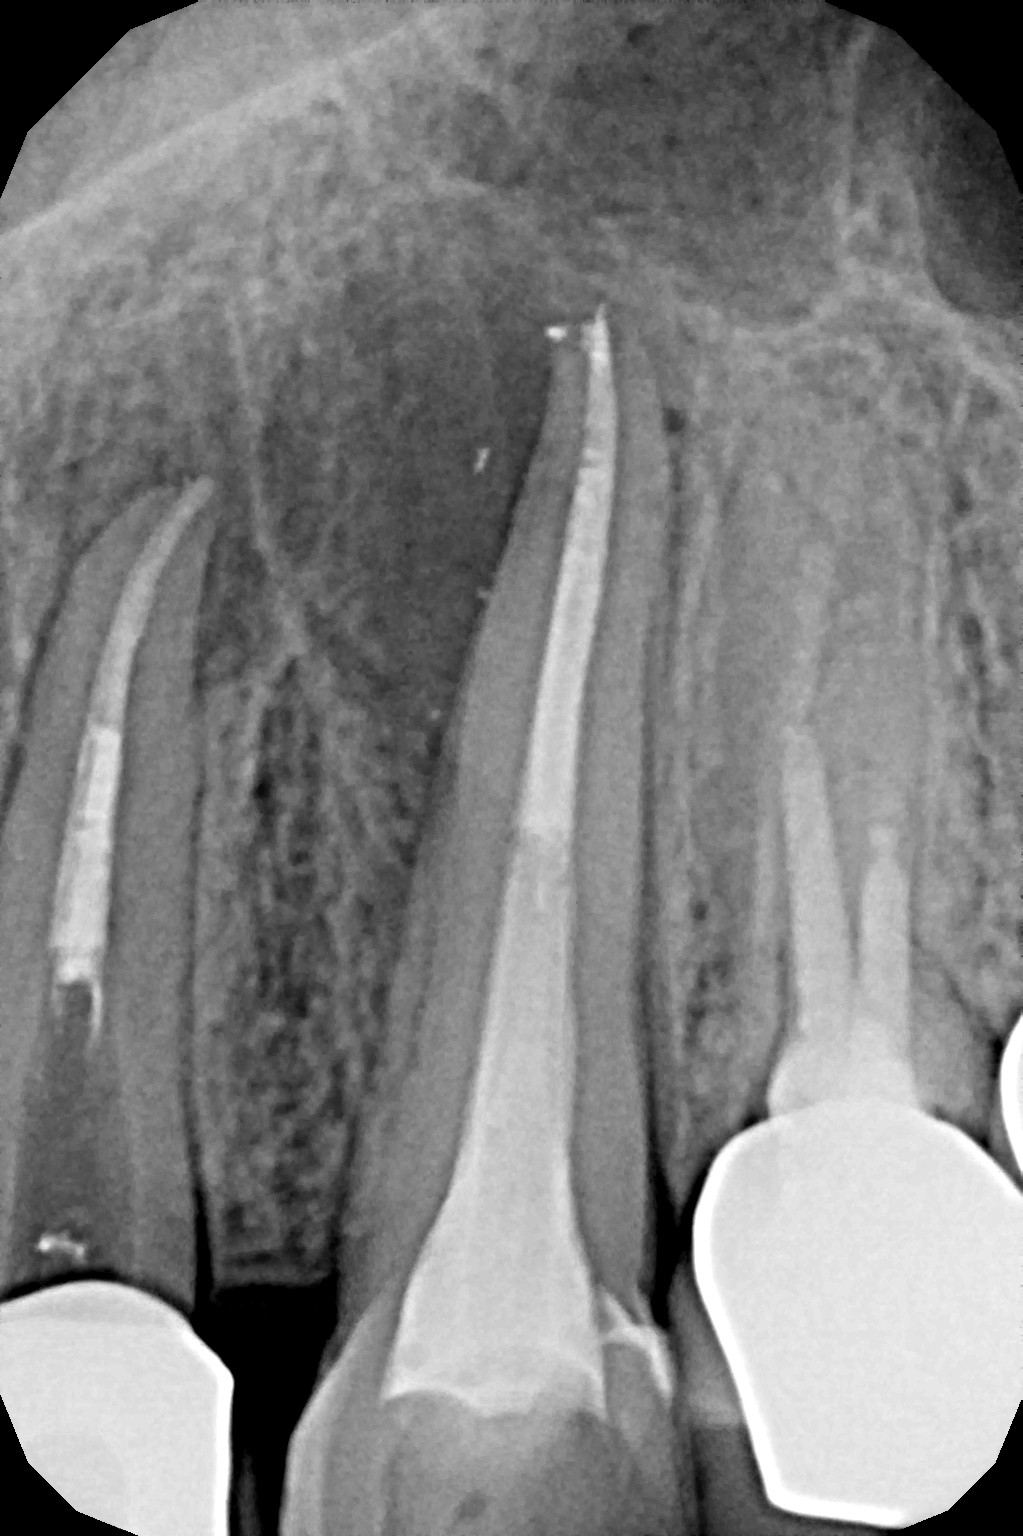

Na podstawie zdjęcia rentgenowskiego określa się kształt i długość kanału bądź za pomocą specjalnego urządzenia mierzy się jego długość. Potem lekarz otwiera wejścia do kanału, chroniąc ząb koferdamem, czyli specjalną gumą, zapewniającą sterylność oraz chroniącą przed środkami chemicznymi służącymi do oczyszczania kanału. Używa się do tego zarówno specjalistycznego sprzętu, jak i nowoczesnych mikroskopów, pozwalających na uzyskanie dokładnego obrazu leczonego zęba. Ostatnią czynnością jest wypełnienie materiałem światłoutwardzalnym i zabezpieczenie zęba przed dostaniem się i rozwojem bakterii mogących wywołać wtórny stan zapalny.

By uniknąć niedokładności leczenia, oprócz sumiennego wykonania procedur należy diagnostycznie kontrolować każdy etap leczniczy przy użyciu rtg. Szansą dla niedokładnie wypełnionego kanałowo zęba jest jego powtórne leczenie endodontyczne, zwane REENDO.